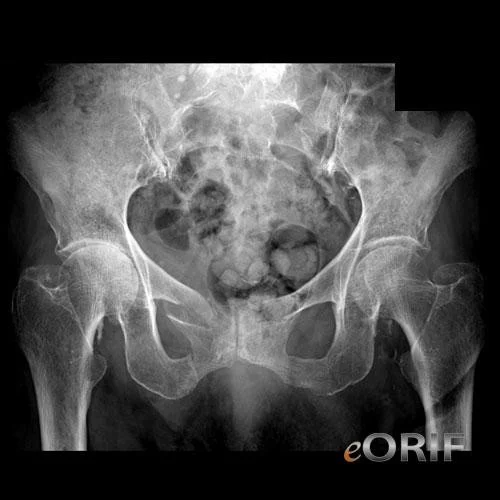

Fractures of Pelvic Ring

In adults, one break in the ring is accompanied by another break in the ring

Three mechanisms:

AP compression

- Anteroposterior compression

- Frontal collision of car-pedestrian

- Pubic rami fractured or

- Disruption of symphysis pubis

- Open-book (stable if <2cm)